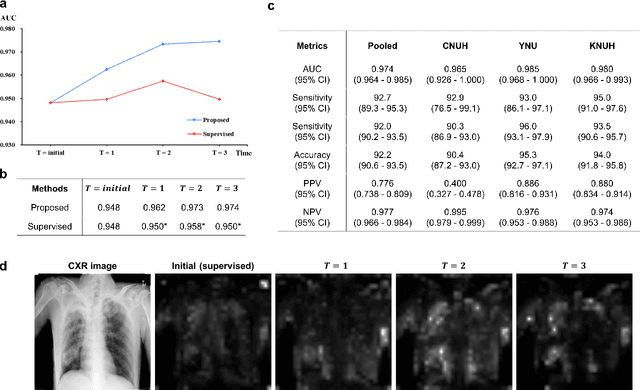

Abstract:Although deep learning-based computer-aided diagnosis systems have recently achieved expert-level performance, developing a robust deep learning model requires large, high-quality data with manual annotation, which is expensive to obtain. This situation poses the problem that the chest x-rays collected annually in hospitals cannot be used due to the lack of manual labeling by experts, especially in deprived areas. To address this, here we present a novel deep learning framework that uses knowledge distillation through self-supervised learning and self-training, which shows that the performance of the original model trained with a small number of labels can be gradually improved with more unlabeled data. Experimental results show that the proposed framework maintains impressive robustness against a real-world environment and has general applicability to several diagnostic tasks such as tuberculosis, pneumothorax, and COVID-19. Notably, we demonstrated that our model performs even better than those trained with the same amount of labeled data. The proposed framework has a great potential for medical imaging, where plenty of data is accumulated every year, but ground truth annotations are expensive to obtain.